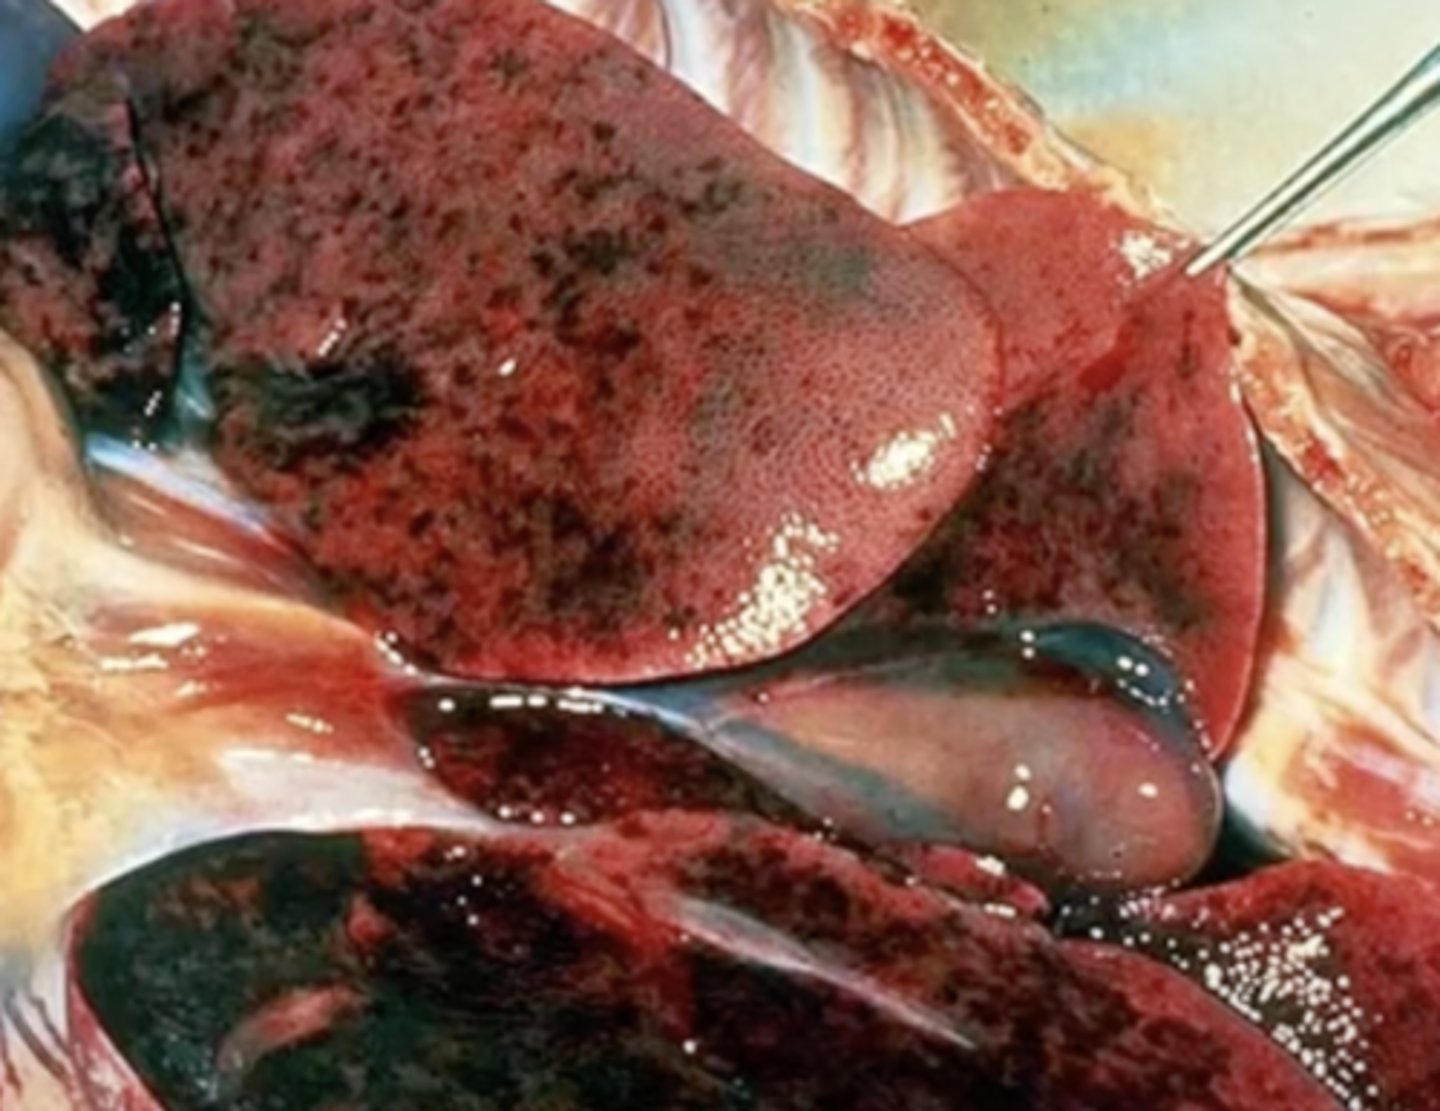

spleen, diffuse enlargement, rounded edges, mottled red color

splenomegaly - splenic lymphoma

Describe this lesion + diagnosis